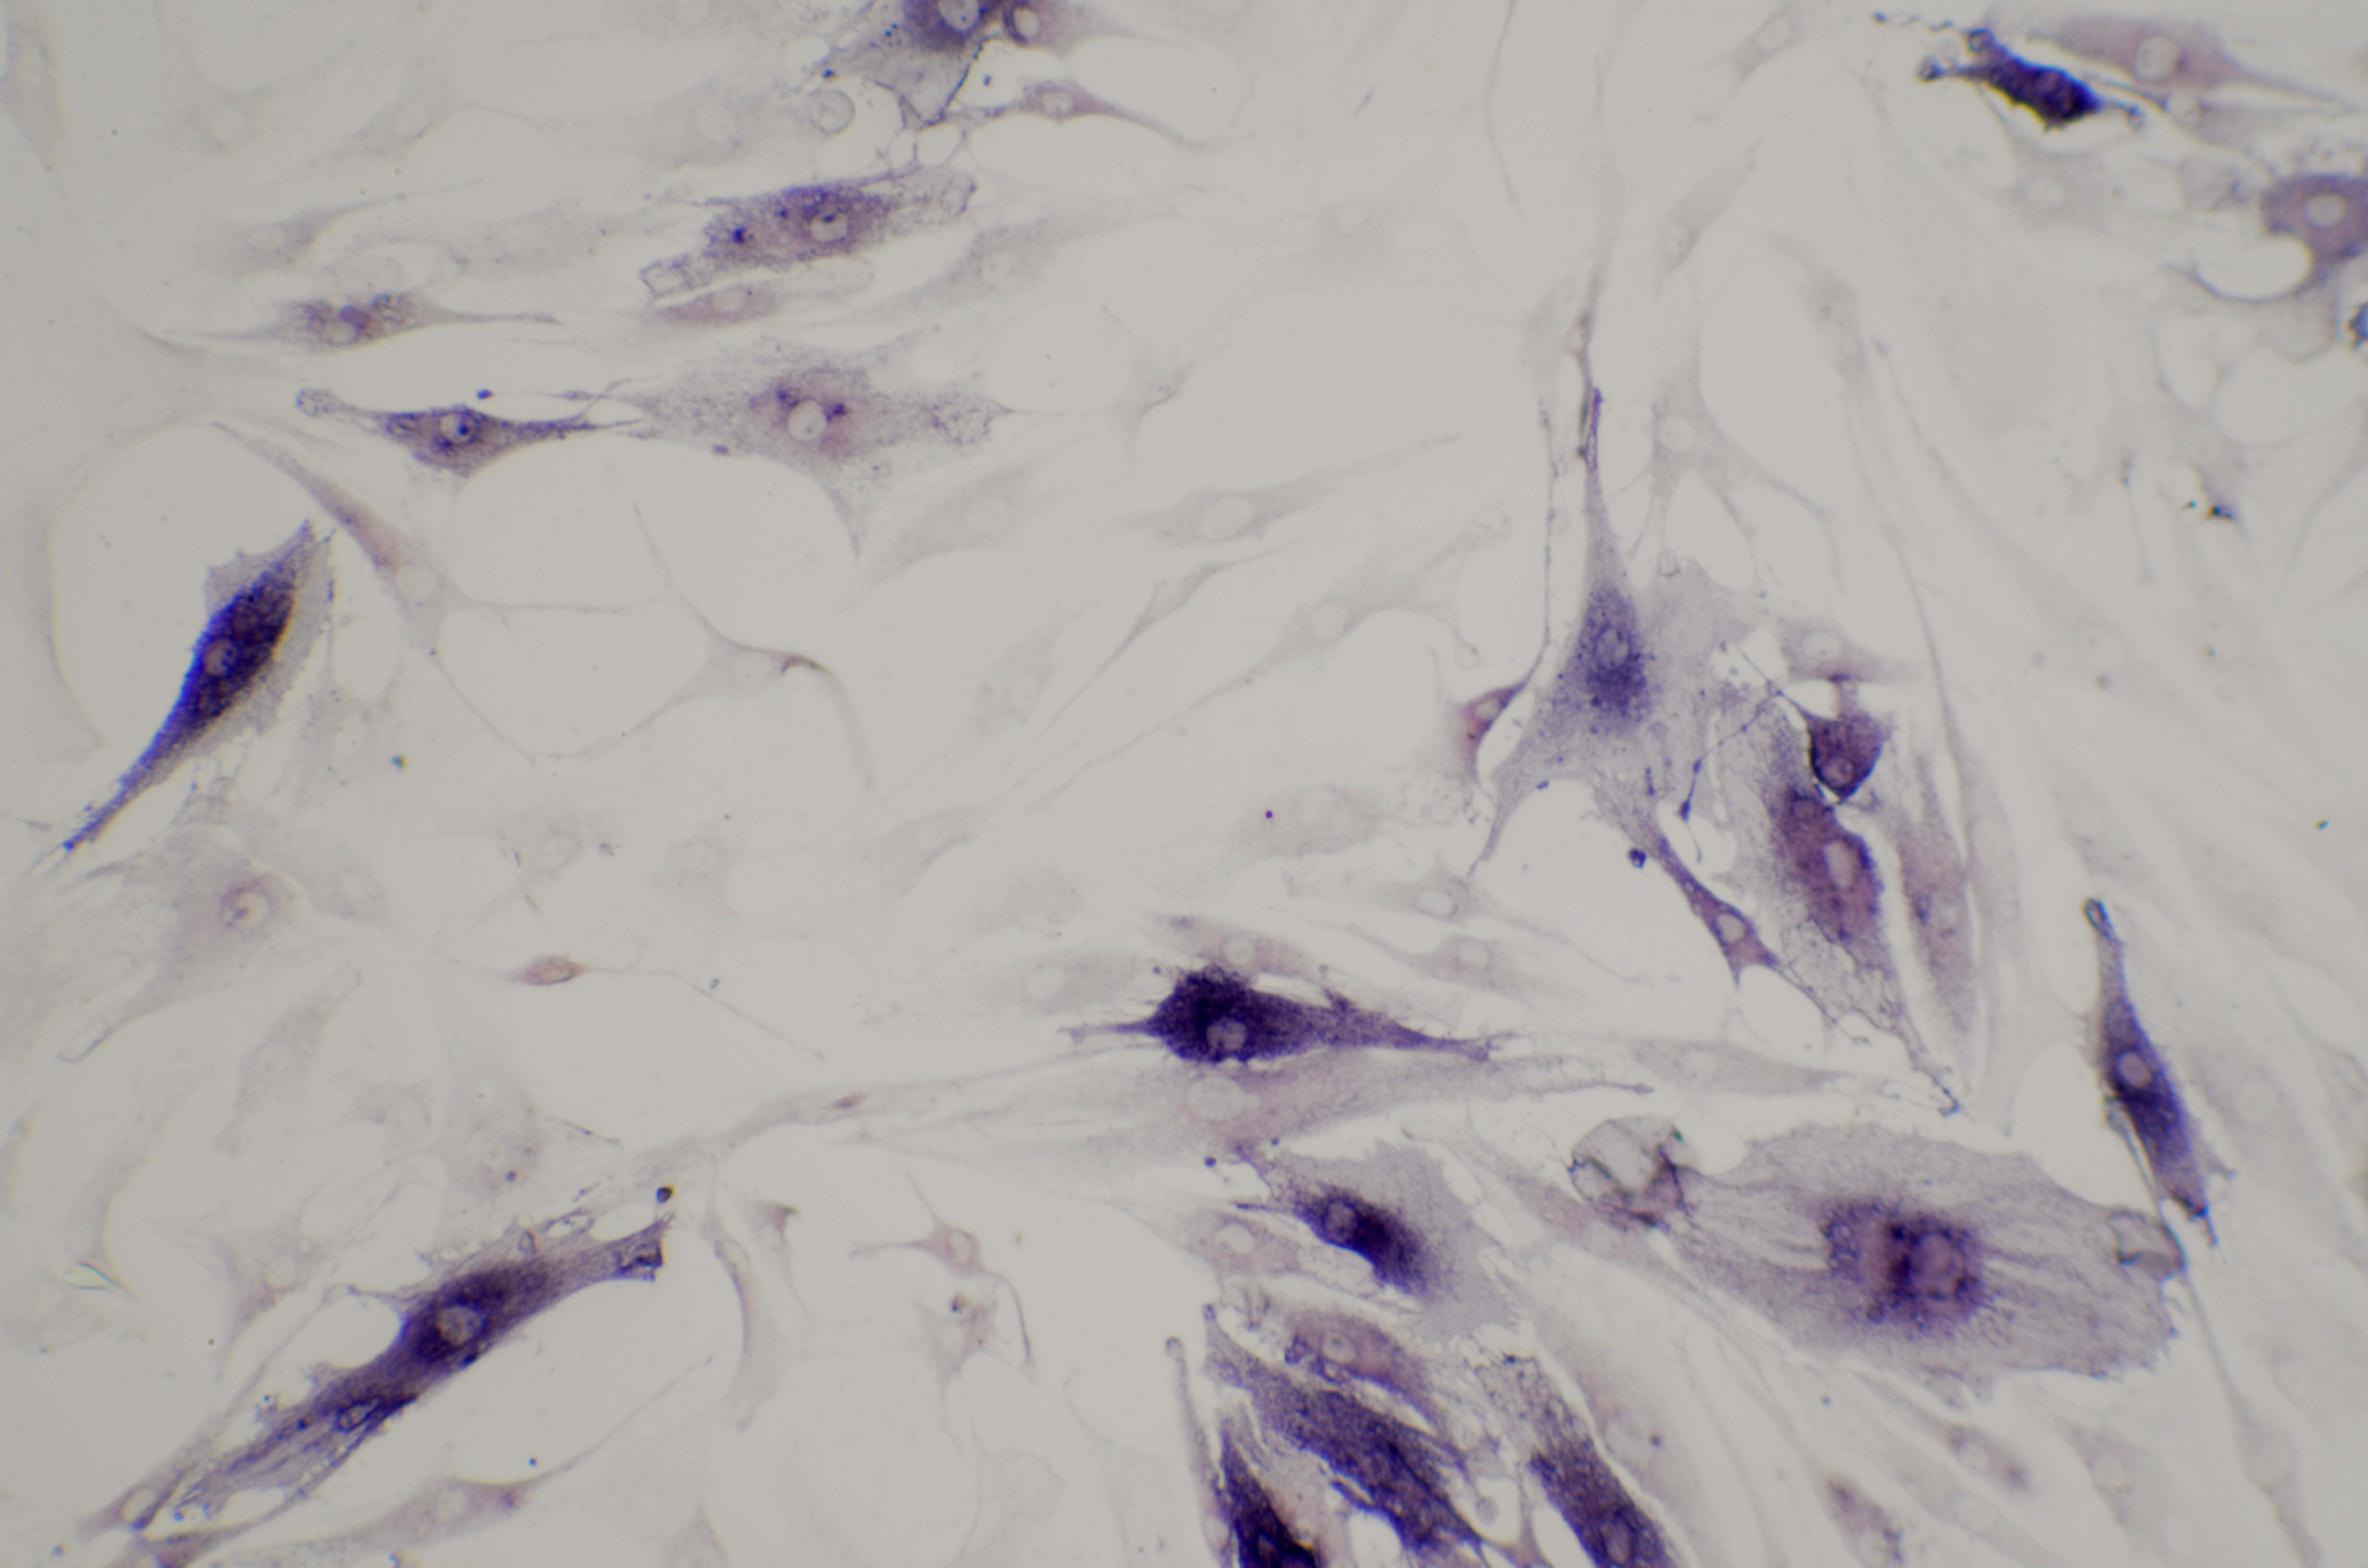

ALP实验